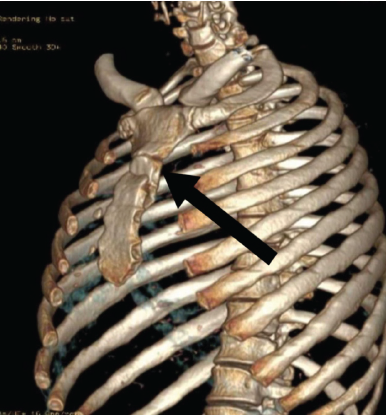

We present a case of 31-year-old male who sustained injury in Road Traffic Accident on May 16, 2024; the patient was initially received and treated in nearby district hospital for complains of chest pain, injury over right leg, B/L wrist, forearm, no history of loss of consciousness, ear, nose, and throat bleed, vomiting noted, Glasgow Coma Scale was 15/15, wound debridement and external fixator applied for comminuted fracture both bone lower one third in right leg, suturing of contused lacerated wound after proper wound wash. After 2 days, the patient came to our hospital for further management; on examination, we found sutured wound with external fixator over the right leg, other sutured wound over the body, patient complained of pain over chest, he had tenderness over sternum with normal breathing pattern; hence, we suspected of chest injury and took computed tomography scan; surprisingly, we found fracture in the upper part of sternal body with displacement, with no other rib fracture nor vertebral fracture with minimal lung contusion (Fig. 1), we also noted undisplaced fracture of right radial styloid process and segmental fibula fracture with comminuted distal third tibia fracture.

Figure 1: Computed tomography scan of the chest showing the displaced upper third of the body of sternum.